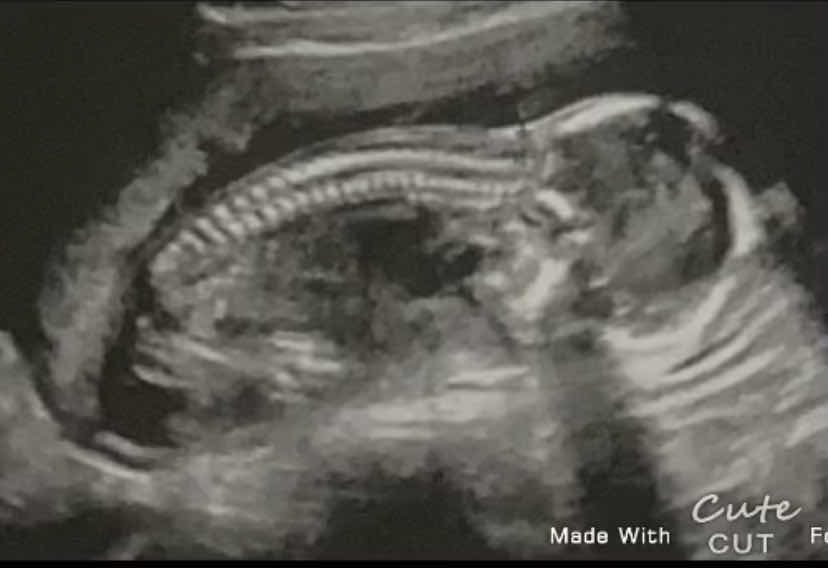

في صوره السنور ثلاثي الابعاد لم استطيع رؤيه ملامح الجنين هنا لا اقصد بها الملامح الدقيقه يأرفق صوره من السونار والرجاء التأمد هل وجه الجنين طبيعي؟

5F526EE7-FA3D-4A96-B2AF-45B68A5E6736

نعم...طبيعي 1 2021-12-09T15:29:16+00:00

نعم...طبيعي